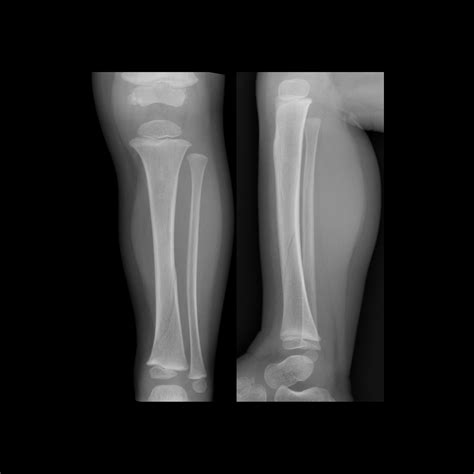

Pediatric Radiology is a subspecialty of radiology focused on the imaging of infants, children, and adolescents. Because children are not simply "miniature adults," their bodies undergo constant growth and development. Bones are still ossifying, organ systems are maturing, and metabolic rates are significantly higher than those of adults. These factors necessitate highly specific protocols for diagnostic imaging.

• X-rays: Often the first line of defense for bone fractures or lung issues.

X-ray Minimal Bone fractures, pneumonia, chest congestion

Furthermore, radiation sensitivity is a biological reality in younger patients. Because children have a longer life expectancy, the theoretical risk associated with cumulative radiation is handled with extreme caution. Specialized radiologists use dose-reduction software and settings tailored specifically to the body size of the patient, ensuring that the child receives the lowest effective dose of ionizing radiation possible.